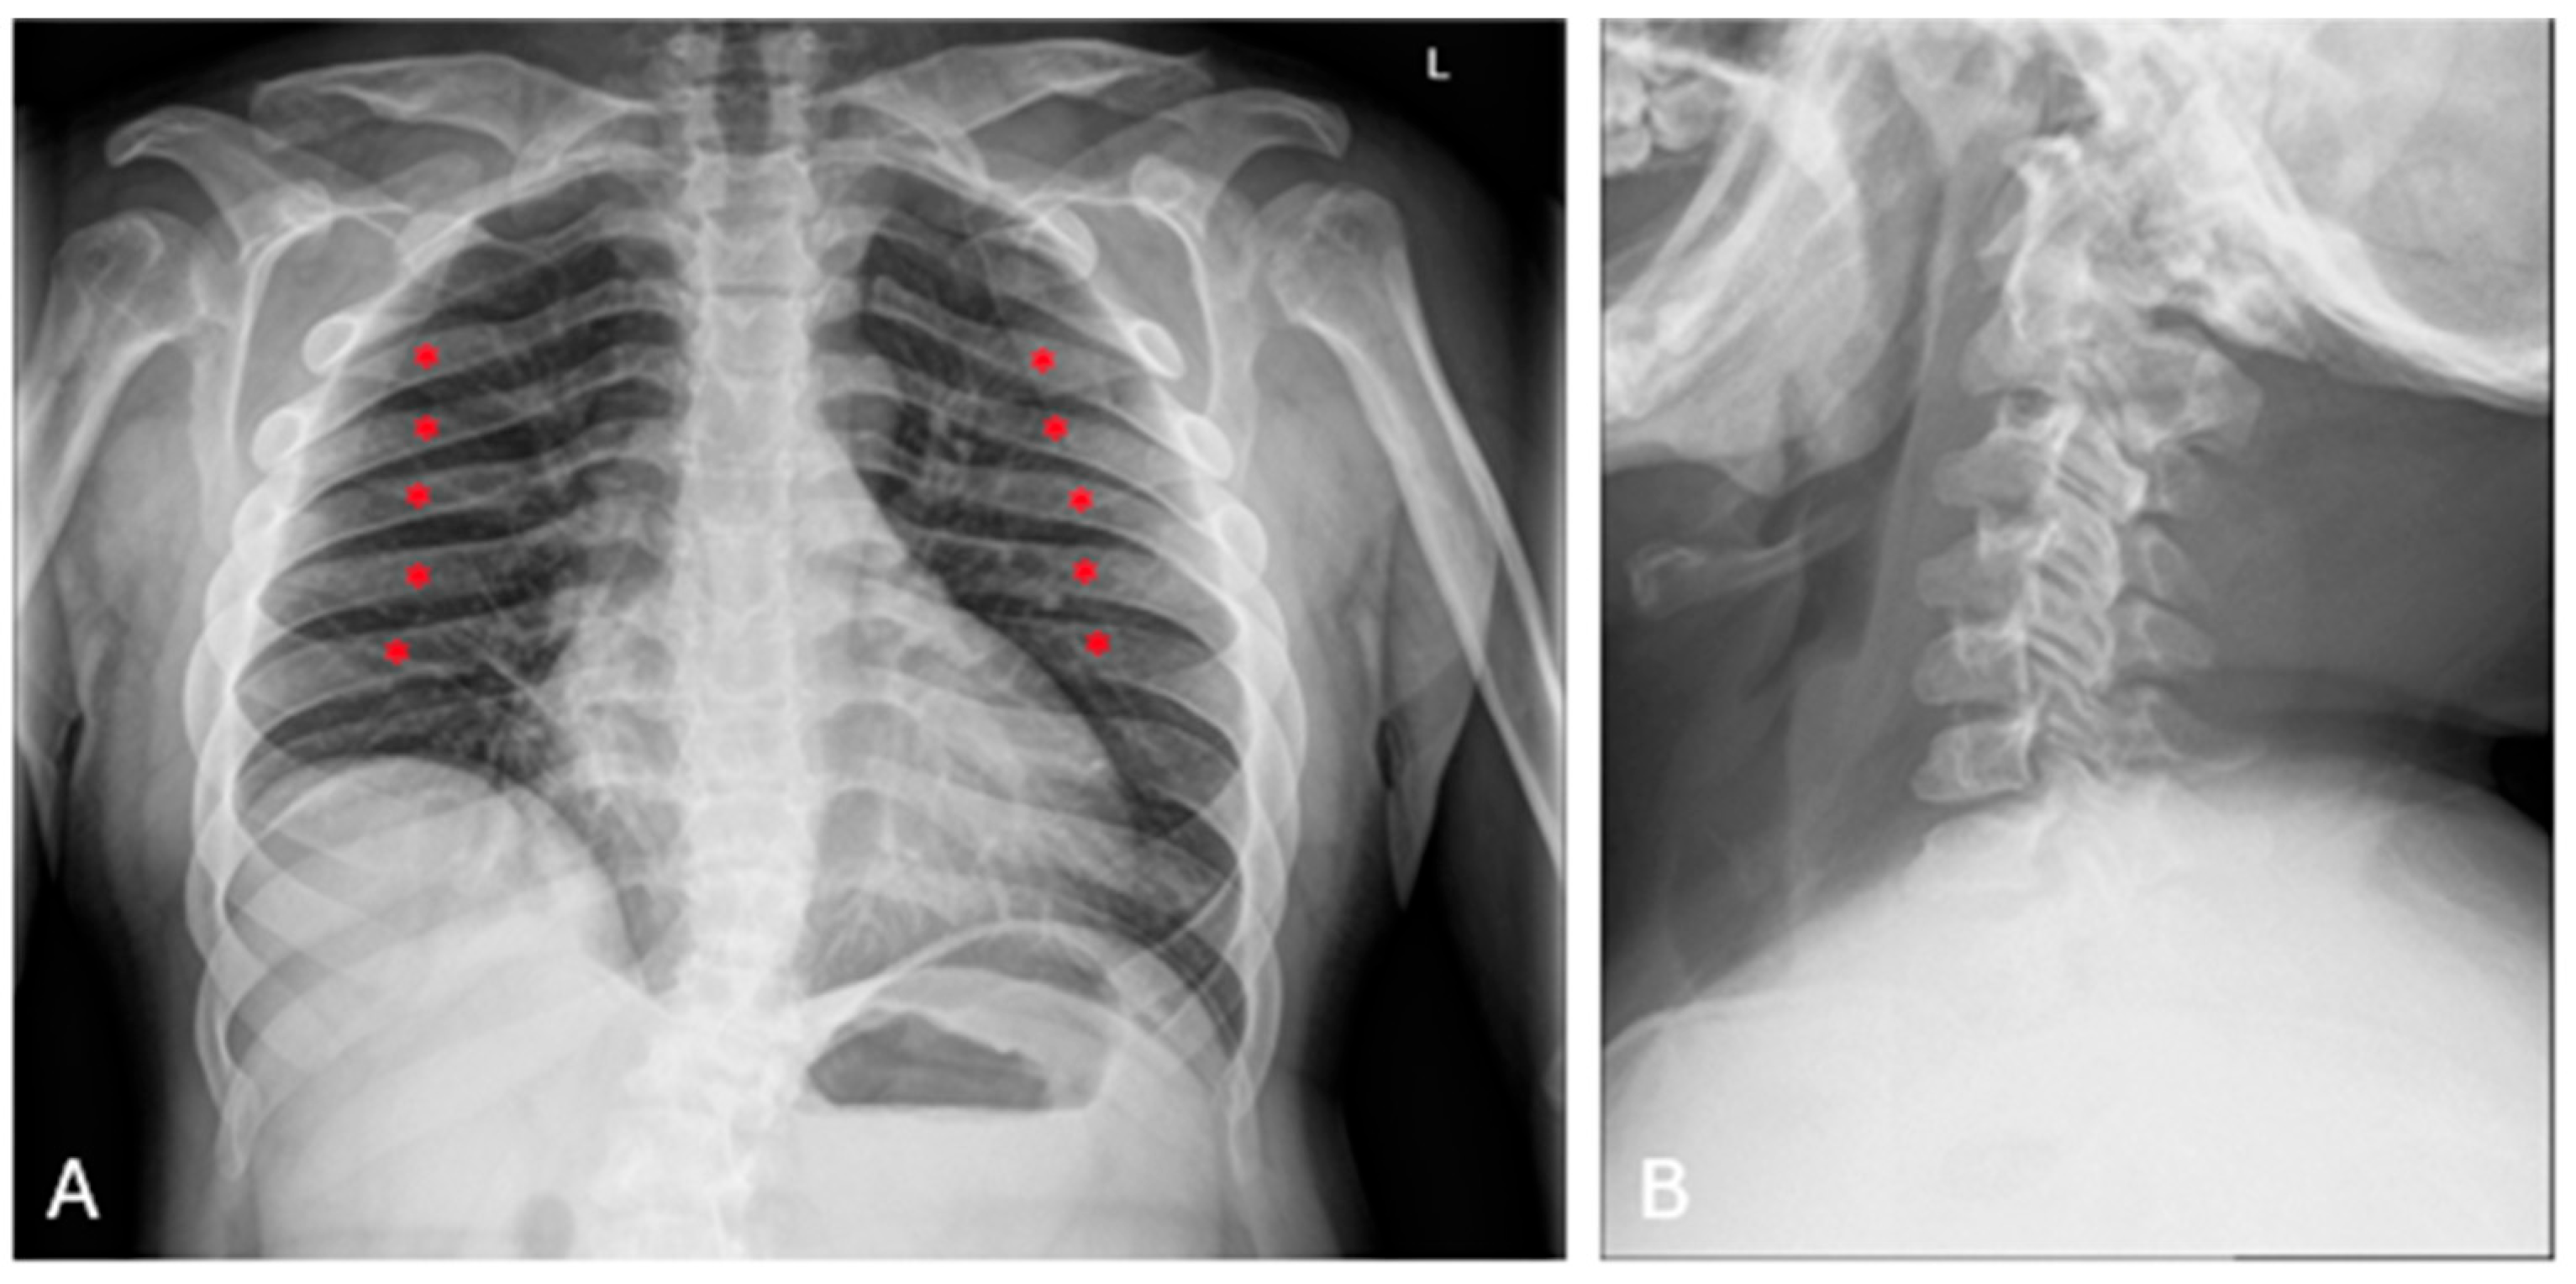

| P6 (MPSIV) | Baseline | CT | Spine | Platyspondyly in both cervical and thoracolumbar regions; anterior vertebral body beaking. |

| After 8 years of ERT | MRI | Spine | Deformities of the vertebral bodies and posterior bulging of the intervertebral discs; spinal canal impression. |